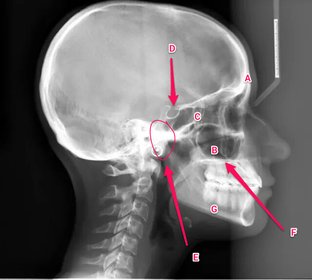

Anatomy practical midyear flashcard revision

anatomy

x-ray